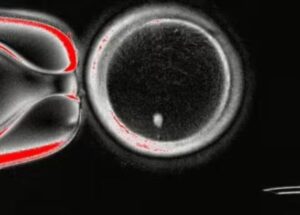

Σύμφωνα με τον τοπικό Τύπο, η γυναίκα διανύει τον έκτο μήνα της εγκυμοσύνης της και οι ειδικοί ανησυχούν για την υγεία της αλλά και για τις πιθανότητες επιβίωσης των επτά εμβρύων.

Η γέννηση επτάδυμων είναι εξαιρετικά σπάνιο γεγονός.